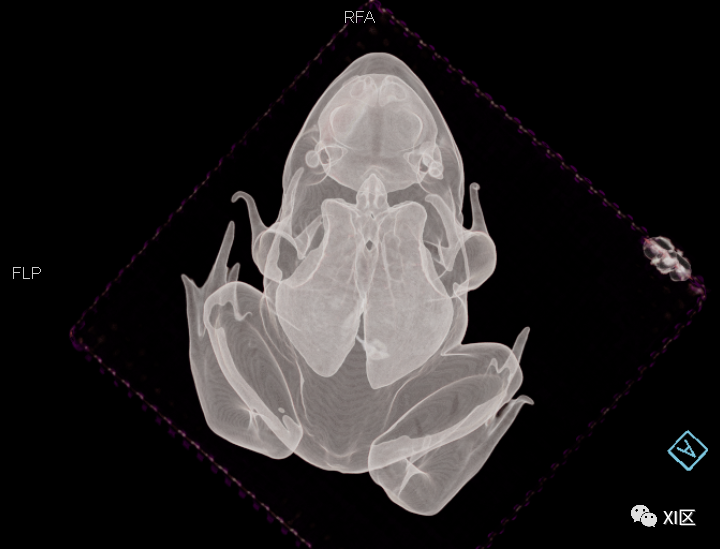

我们带一只牛蛙作为代表

进行了一次CT检查

正在接受CT检查的牛蛙

本次扫描使用的设备是SOMATOM go.Top

为了了解牛蛙的全身结构

我们给他进行了一次全身CT扫描

并进行了三维重建

先来欣赏一下三维重建的效果

牛蛙的三维重建

牛蛙的三维重建,显示牛蛙肉、肺和骨骼